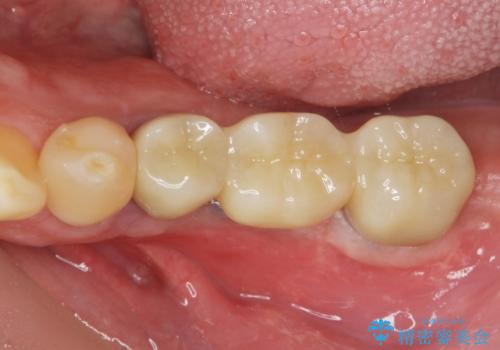

臼歯部インプラント補綴

- 奥歯で物が噛めず、食事が楽しめなくなってしまった。しっかり噛んで食事ができるようになりたいと来院されました。

予後の不安な小臼歯と、すでに大臼歯は2本喪失した状態で咀嚼機能に大きく問題がある状態です。

グラつきのある小臼歯は、抜歯を行い2本のインプラントを埋入することでしっかりと咬合機能を回復できる治療を計画します。

- 89.1万円(仮歯×3・ストローマンインプラント×3・フルジルコニアクラウン×3・チタンカスタムアバットメント×3)費用は治療当時の料金となります

インプラントは複数の奥歯を失った際に、咬合機能をしっかりと回復できる有効な治療です。

治療後はまたしっかりと噛んで食事を楽しむことができるようになったと喜んでいただくことができました。